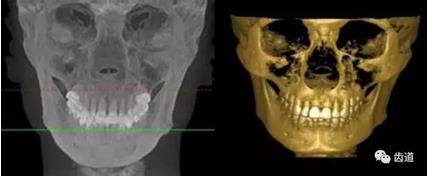

五)口腔正畸

CBCT在頜骨正畸科方面的應(yīng)用:軟件功能的強大,提供有效的數(shù)據(jù),為頜骨正畸提供了極大的幫助,免除了很多臨床醫(yī)生的手工繪圖,并有利于科研、教學(xué)等方面發(fā)展研究。

投影測量側(cè)位片影像

軟件產(chǎn)生CEPH圖像注釋,不含X線射線圖像

軟件產(chǎn)生的數(shù)據(jù)庫

總結(jié)

隨著牙科三維CT在口腔醫(yī)學(xué)臨床的廣泛使用,其分辨率高,定位準(zhǔn)確,圖像清晰,避免重疊的特點必將使口腔醫(yī)學(xué)的診斷和治療獲得深入的發(fā)展,給臨床醫(yī)生和患者帶來福音,同時也為醫(yī)院的服務(wù)質(zhì)量帶來提升。